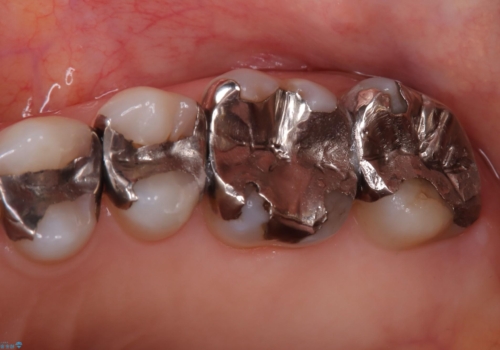

- 主訴:詰め物と歯の境目に穴が空いているとクリーニング時衛生士から指摘された。

保険適用のメタルインレー歯質の境目が虫歯になっていたため、一度メタルインレーを除去し虫歯の範囲の把握と補綴物のやり替えをお勧めし、ジルコニアクラウンでのやり替えとなりました。

保険適用のメタルインレーと歯質の境目にう窩ができており、補綴物のやり替えとなりなした。